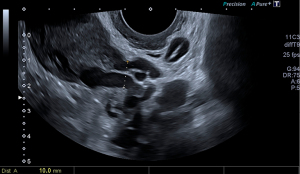

The selected model was Model 3, which identified the presence of a pelvic vein or venous plexus of 8 mm or greater, as predictor of the venographic diagnosis of PCS. Model 3’s Harrell’s C-index obtained from the AUC of the predicted probabilities was 0.79 (95% CI: 0.63–0.96; P<0.001), with a sensitivity of 0.90 and specificity of 0.69 (Figure 2). Table 4 displays the contrast between Model 3 and the gold standard, which shows a sensitivity of with a sensitivity of 86.05%, a specificity of 66.67% and a positive predictive value of 86.05% (Table 5). Ultrasonography captions of the measurement of pelvic vein and venous plexus are displayed in Figures 3,4.

Ultrasonography evaluation was carried out by an expert in gynecological ultrasound, with more than 15 years of experience, using a Canon Aplio 500 (Toshiba Medical systems Corp., Tokyo, Japan) with a 6.5 MHz probe. Set-up of the 2-D mode consisting in the use of 2 focal zones, with an 80–95 gain, dynamic range of 60–75. For the use of color and spectral Doppler the size of the Doppler sampling window was set at 45×45 mm, color gain between 35–45 and PRF at 5.4–7.6 cm/s. In order to carry out the examination while the bladder was empty, as is customary, patients were asked to adopt the gynecological position short after urinating. The assessment started first by completely assessing the uterus and the adnexa in a longitudinal and cross-sectional plane. We used the simplified prolate ellipsoid formula to calculate uterine and ovarian volumes. Afterwards, the uterine vein was tracked from its origin at the internal cervical os up until the internal iliac veins and collateral branches, in order to identify the largest pelvic vein as well as the venous plexus. These were measured in their anteroposterior diameter in a cross-sectional plane. For the Doppler assessment of the pelvis, we identify the flow direction with color and spectral Doppler and asked the patient to perform a Valsalva maneuver to identify changes in the flow velocity. This procedure was first performed in one side and then repeated for the contralateral side. Subsequently, we applied color Doppler in a cross-sectional plane of the uterus determine whether there were crossing veins in the myometrium, then measured its maximum anteroposterior diameter. Thus, we collected the following ultrasonographic variables: uterine volume, right and left ovarian volume, presence of polycystic ovaries (PCO), inner diameter of the largest pelvic vein (right and left side), maximum diameter of the largest venous plexus (right and left side), reverse or altered flow during Valsalva, presence of crossing veins in the myometrium, and maximum diameter of crossing veins in the myometrium.